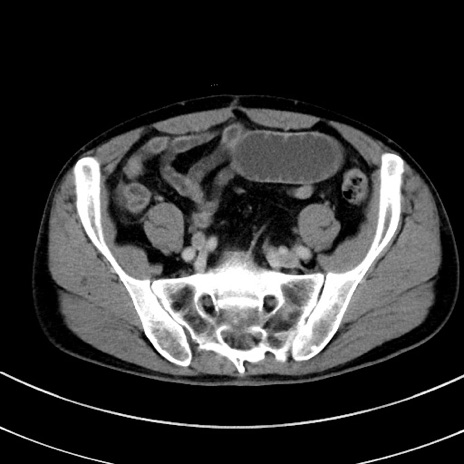

症例8(横断像)

【症例】 60歳代男性

【主訴】 黒色吐物

【現病歴】 4日前から嘔気自覚、2日前の朝食後にも嘔気あり、自分で手で嘔吐反射起こし嘔吐したところ血が混ざっていたため受診。

【既往歴】 5年前汎発性腹膜炎を伴う急性虫垂炎で手術、高血圧、前立腺肥大症、高脂血症

【身体所見】 腹部正中に手術癩痕あり 腹部平坦・軟圧痛なし膨満感あり

【データ】WBC 8400、CRP 4.54